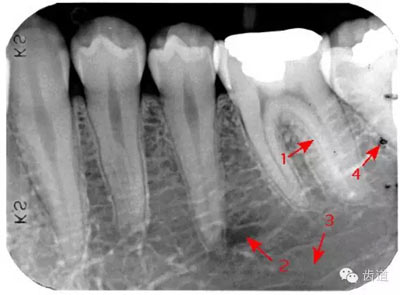

是機體中鈣化最高和最堅硬的組織,X線片上的影像密度也最高,似帽狀被覆在牙冠部牙本質(zhì)的表面。后牙頜面、前牙切緣最厚,由頜面和切緣向側(cè)方至牙頸部逐漸變薄,終止于牙頸部。

圍繞牙髓構(gòu)成牙的主體,牙本質(zhì)中礦物質(zhì)的含量比釉質(zhì)少,X線影像的密度較牙釉質(zhì)稍低。

被覆在牙根表面,為一層很薄的組織,密度與牙本質(zhì)相當(dāng) 。

髓腔可分為冠部的髓室和根部的根管。牙髓內(nèi)含牙髓軟組織,X線片上顯示為密度低的影像。年輕人的牙、牙根未完全形成時,根尖孔粗大,牙髓腔大。隨著年齡的增長,牙本質(zhì)逐漸增多,髓腔愈狹窄,根尖逐漸變細(xì)。

即固有牙槽骨,是牙槽骨的內(nèi)壁,圍繞牙根,骨質(zhì)致密而薄,X線片上顯示為包繞牙根的連續(xù)不斷的密度高的線條狀影像。

是介于牙槽窩和牙骨質(zhì)之間的結(jié)締組織。牙周膜的厚度一般在0.15~0.38mm之間。X線上顯示為包繞牙根連續(xù)不斷的密度低的線條狀影像,其寬度均勻一致